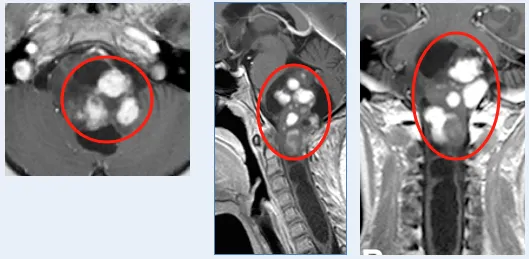

经过严谨的评估,巴教授认为Emma的肿瘤类型和位置,符合手术适应症,存在安全切除的可能性。

手术台上,在神经电生理监测的“实时警报”下,巴教授以精湛的技艺,小心翼翼地避开关键神经结构,最大限度地切除了肿瘤。